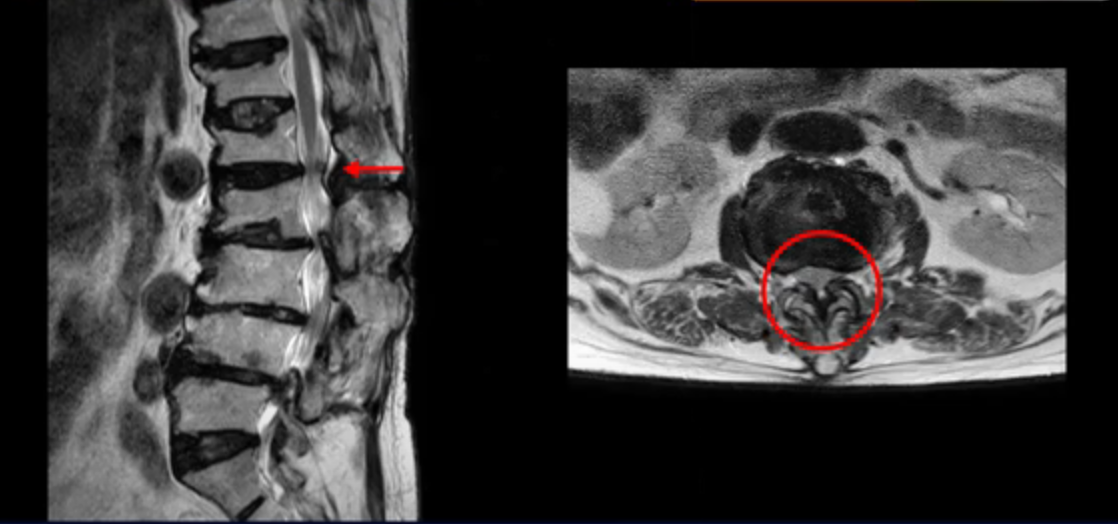

보시다시피 4번 5번 마디에는 심한 중심성 협착이 있고

3번 4번에도 중심성 협착이 있습니다.

또 신경 가지가 빠져나가는 추간공도 좁아져 있습니다. 이런 이유로 환자분의 다리가 저리고 아픈 겁니다.

골다공증도 심하시고 보시다시피 근육량이 너무 적습니다. 근육이 정상적인 분들과 비교해보면 근육이 얼마나 적은지 알 수 있습니다.